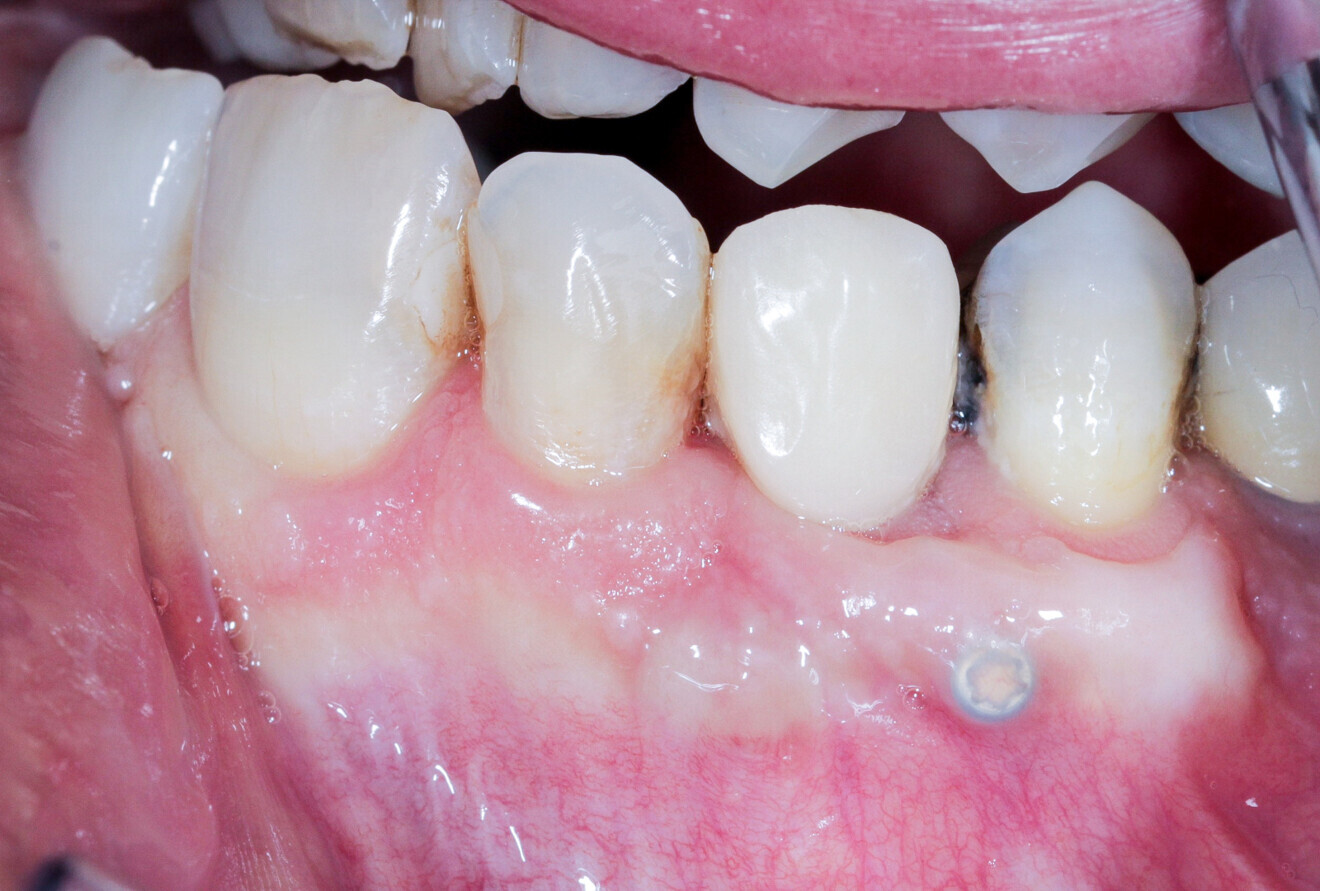

A 62-year-old patient with a bridge from tooth #21 to tooth #27 requiring replacement, teeth #21, 23, 24 and 27 with abutments and the crown of #22, 25 and 26 missing, was treated. The ridge of tooth #22 exhibited a transverse bone insufficiency which would have allowed the placement of an implant, but the aesthetic outcome would have been unsatisfactory (Fig. 10). First, the bridge of tooth #24 was sectioned distally and the root of tooth #27 extracted. After a two-month healing period, the patient was treated with simultaneous extraction, implantation and aesthetic restoration. The bridge was sectioned distally at tooth #21, a full thickness flap was elevated and the teeth #23 and 24 were extracted, allowing the bone defect at tooth #22 to be assessed (Fig. 11). Implants were placed into sites #22, 24 and 27. The root of tooth #23 allowed us to compensate for the bone defect and achieve a satisfactory aesthetic result. The root was prepared as described. The radicular graft was fixated away from the ridge, the edges of the graft in contact with the alveolar bone (Fig. 12). The spaces between the ridge, the graft and the alveoli were filled with a synthetic, hydroxyapatite-based biomaterial, the flap was stretched and sutured around the healing abutments, an impression was taken, and a temporary prosthesis from implant #22 to 27 was made during the day by the laboratory and fitted the same evening. The stitches were removed on the tenth day and the bridge after two months to check for the successful osseointegration of the implants. The osteosynthesis screws were not removed in this case because they were not visible under the gingiva (Figs. 13 & 14). A CBCT assessment was performed after six months to check that the graft had taken successfully. Finally, our colleague fitted the definitive prosthesis.

Case 2